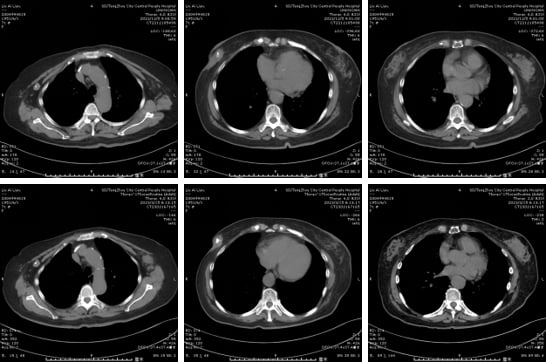

患者最初接受了多西他赛、环磷酰胺、表阿霉素的化疗方案。然而,在治疗过程中出现了严重的IV度骨髓抑制(白细胞和中性粒细胞极低),并伴有发热,提示患者对该方案耐受性差。医生团队迅速调整策略,更换为靶向联合化疗方案:曲妥珠单抗(赫赛汀)联合多西他赛和卡铂(TCbHP方案)。曲妥珠单抗作为HER2靶向治疗的基石,能够精准阻断HER2信号通路。调整后的方案患者耐受性良好,肿瘤也得到了有效控制,右乳肿块从5.2cm缩小至2.8cm,为后续治疗奠定了基础。

由于患者的心脏功能问题(频发室性早搏),暂时无法进行手术。医生决定转为一线维持治疗,目标是控制肿瘤进展并改善心脏功能。第一阶段尝试了曲妥珠单抗联合卡培他滨,但患者出现重度呕吐,无法耐受。再次调整后,采用曲妥珠单抗联合内分泌药物来曲唑。内分泌治疗对于HR阳性乳腺癌患者尤为重要。经过5个月的治疗,肿瘤稳定(SD),心脏功能也得到明显改善,早搏次数显著下降。这体现了在治疗过程中,医生对患者整体状况的全面考量和个体化方案的灵活调整。

二线治疗(2018.8-2023.3):局部复发,靶向联合放疗精准打击

三线治疗(2023.3-2024.7):对侧乳腺新发病灶,双靶联合化疗再出击

四线治疗(2024.7-2025.2):ADC药物登场,恩美曲妥珠单抗显身手

五线治疗(2025.3-至今):德曲妥珠单抗持续抗癌,疗效显著

2025年3月,患者开始接受目前最先进的ADC药物之一——德曲妥珠单抗(T-DXd)治疗。德曲妥珠单抗同样是ADC药物,它将抗HER2抗体与拓扑异构酶I抑制剂偶联,具有更高的药物抗体比(DAR),意味着每个抗体携带的化疗药物更多,且其化疗载荷在肿瘤微环境中释放后,还能穿透细胞膜,对周围的癌细胞产生“旁观者效应”,进一步增强抗肿瘤活性。截至目前,患者已接受9个周期的T-DXd治疗,左侧腋窝淋巴结较前变小,左乳不规则软组织密度范围缩小,病情持续稳定,且不良反应轻微,耐受性良好。这再次证明了新一代ADC药物在HER2阳性乳腺癌后线治疗中的卓越疗效和安全性。